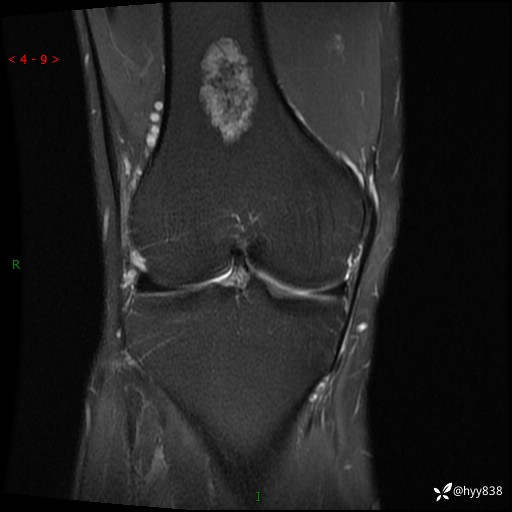

患者性别:男

患者年龄:60岁

主诉:右大腿疼痛不适数月

膝关节平片

MRI

内生软骨瘤 (27)